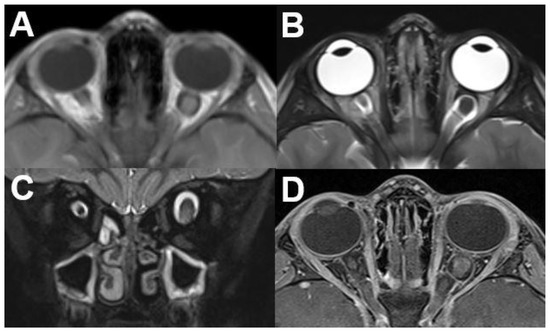

3.1. Intraocular Tumors

3.1.1. Retinoblastoma

3.1.2. Uveal Melanoma